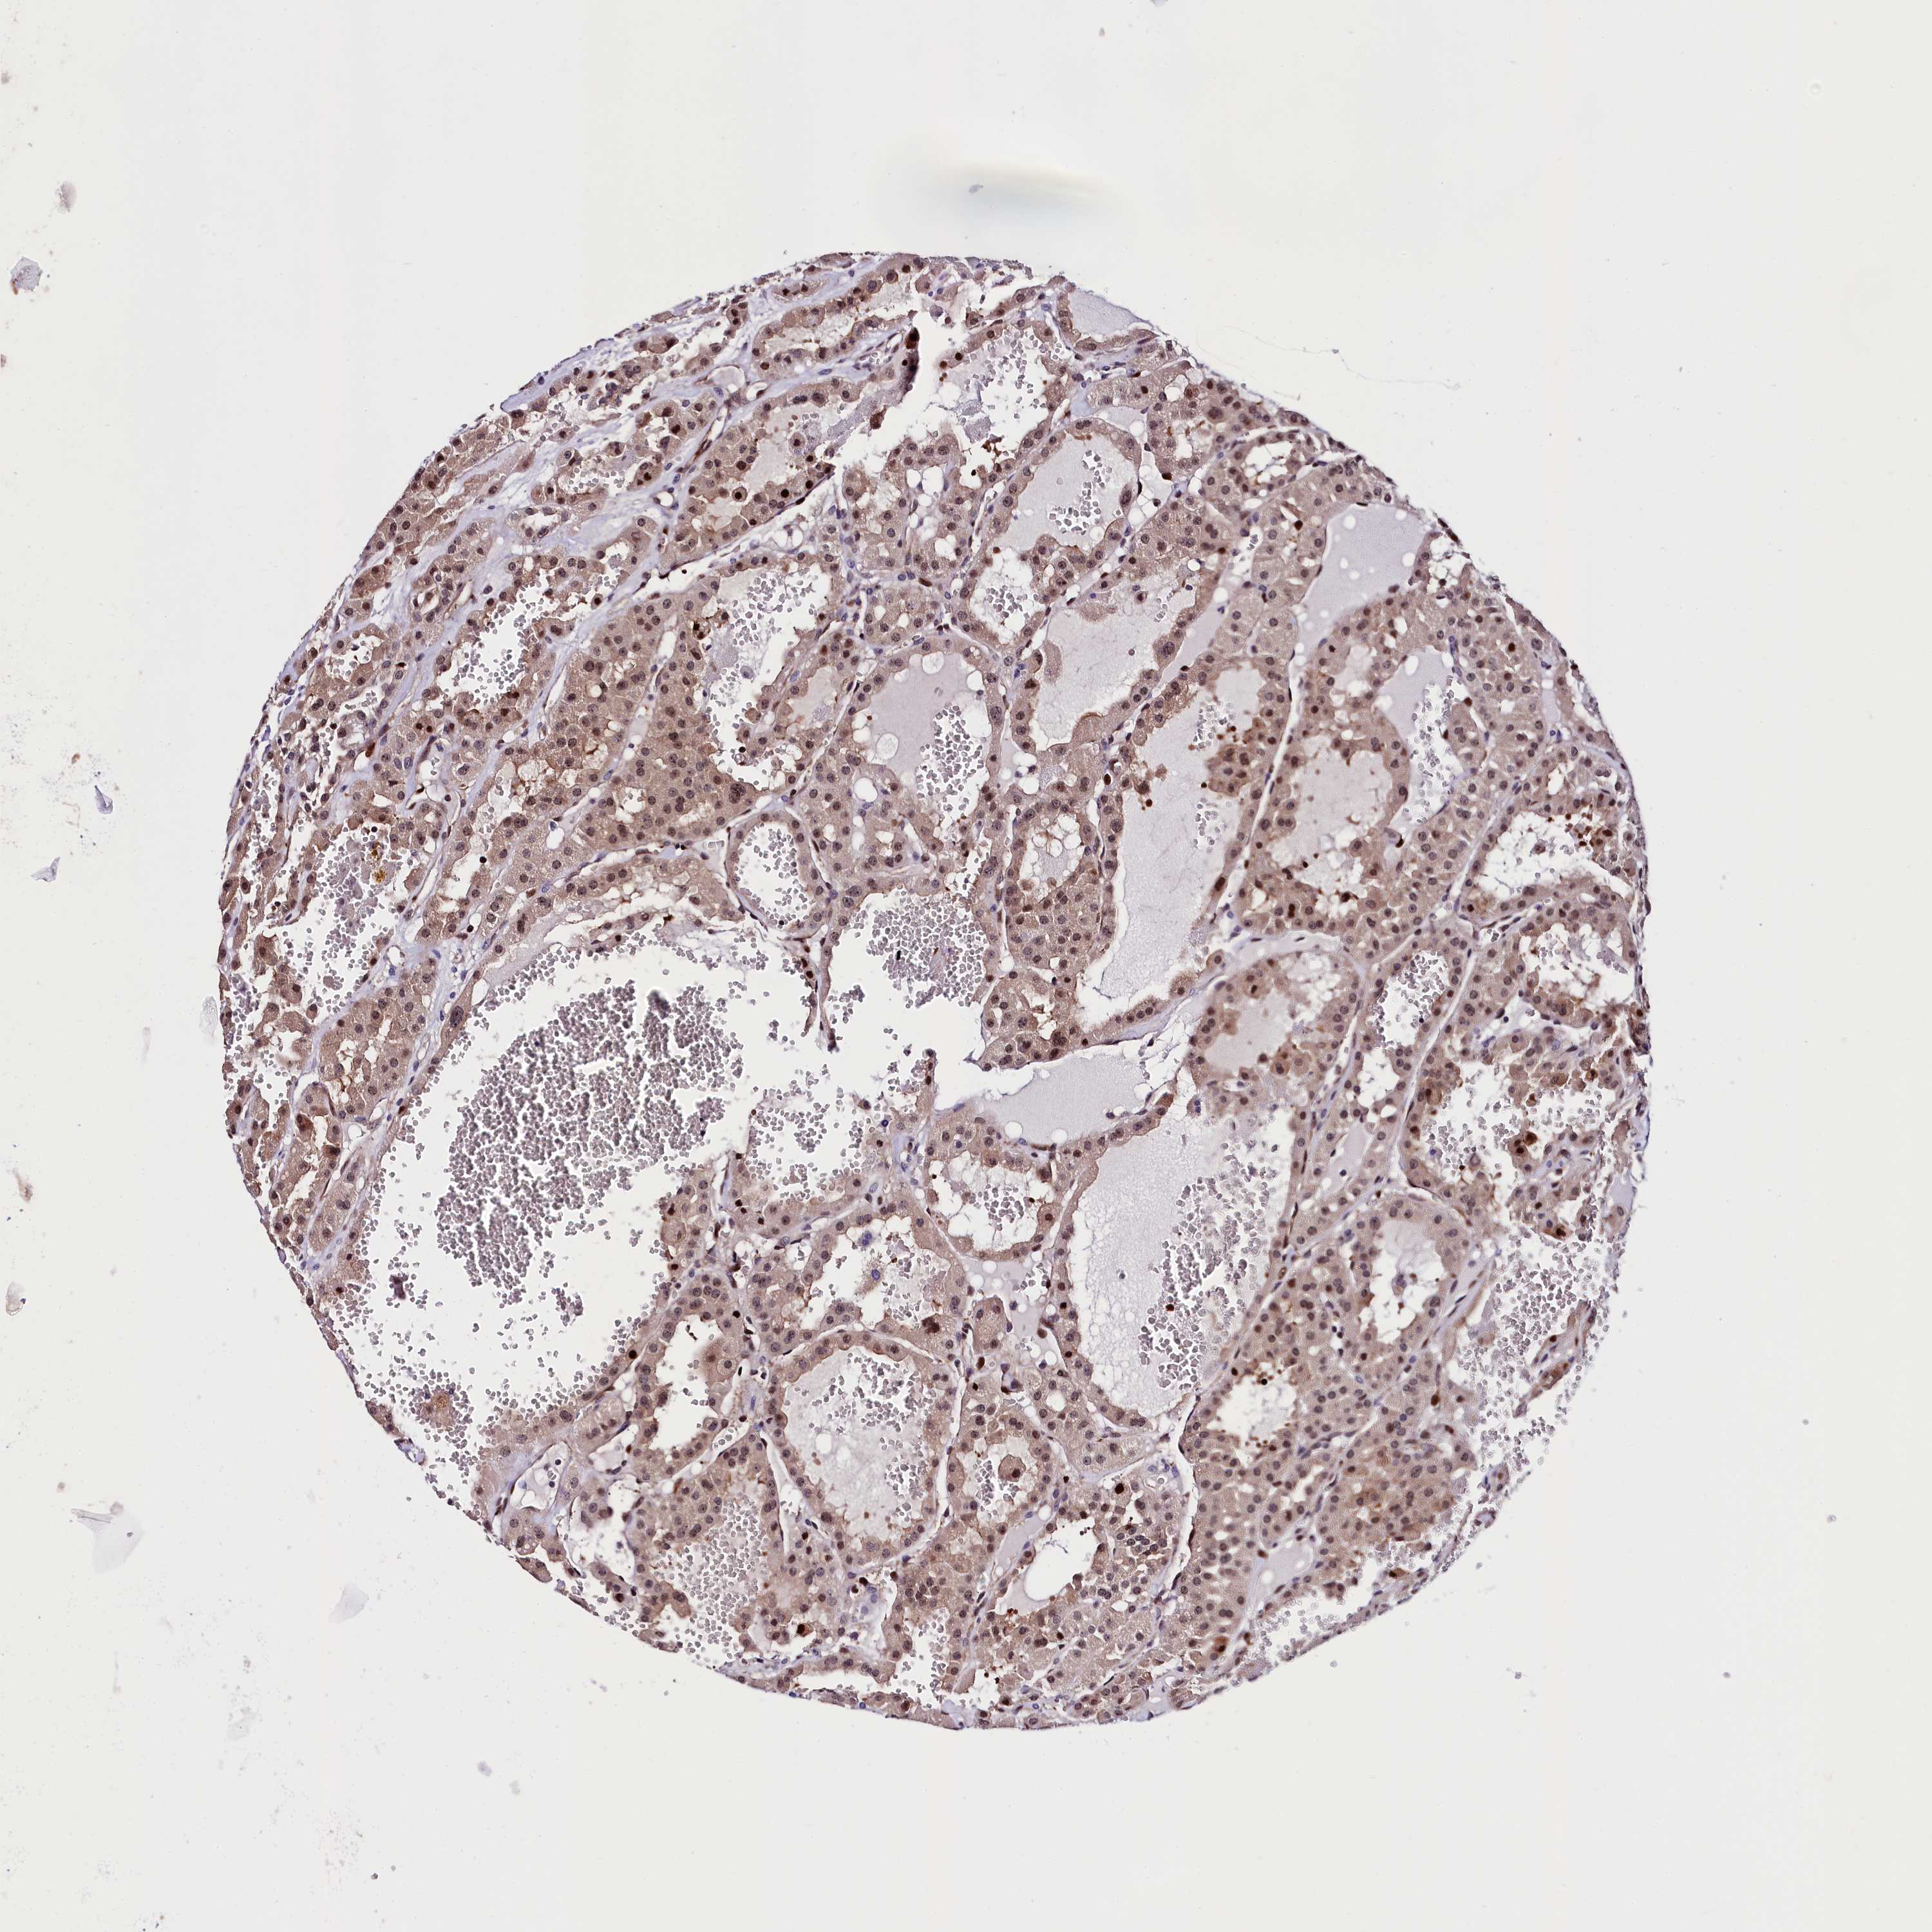

CANCER RENAL CANCER Show tissue menu

KICH TCGA KIRC TCGA KIRC VALIDATION KIRP TCGA PROTEIN RCC CPTAC PROTEIN EXPRESSION